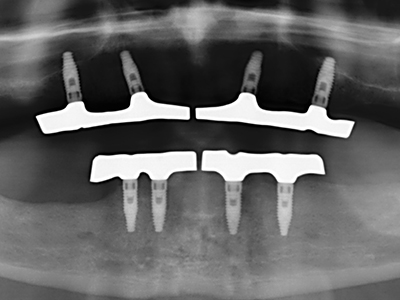

Както е показано в миналото, всяка костна хирургия представлява възможна индикация за пиезохирургия. По този начин, за препарацията на подвижни сегменти в остеогенеза (Фиг. 23-25) и остеотомия се използват специални накрайници, без да се застрашава снабдяването с кръв в кресталната зона, което е от съществено значение за успеха и на двете техники (Gonzalez-Garcia, Diniz-Freitas et al. 2008).

За отстраняването на имплант, вестибуларното костно покритие, което е заменено след премахване на импланта, може да бъде оформено, за да задържи контура на алвеоларния гребен.

Чисто ортодонтските индикации включват ортогнатна хирургия, генопластика (Фиг. 27-30) и орбитална декомпресия при пациенти с напреднала ендокринна орбитопатия, в резултат от Базедова болест (Ponto, Zwiener et al. 2014). Пиезо апаратите се използват също за лицево-челюстна хирургия и за отстраняване на тумори в основата на черепа в различни болници.